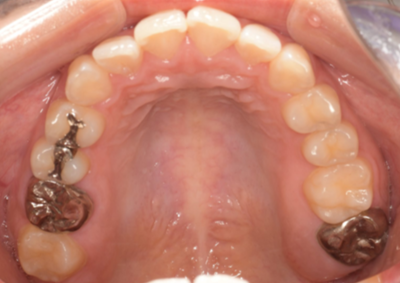

移植12ヶ月後の口腔内写真

移植12ヶ月後。セラミッククラウンで歯冠を修復した。

デンタルX線写真では透過像もほぼ消失している。